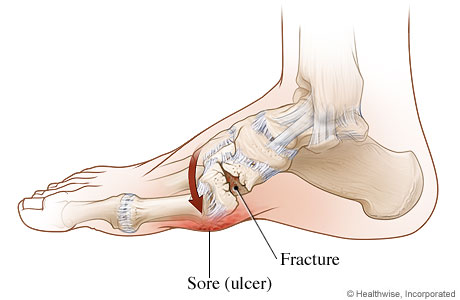

Bệnh khớp Charcot là một tình trạng tiến triển đặc trưng bởi trật khớp, gãy xương bệnh lý và biến dạng nặng ảnh hưởng đến chức năng. Rối loạn này dẫn đến sự phá hủy dần dần xương và mô mềm ở các khớp chịu trọng lượng và ở dạng nghiêm trọng nhất có thể gây ra sự phá vỡ đáng kể cấu trúc xương. Tình trạng này có thể ảnh hưởng đến bất kỳ khớp nào; tuy nhiên, nó xảy ra phổ biến nhất ở chi dưới ở bàn chân và cổ chân.

Bệnh khớp Charcot rất có thể là kết quả của sự kết hợp của các cơ chế này. Bệnh lý thần kinh tự chủ dẫn đến sự tạo xương bất thường, còn bệnh lý thần kinh cảm giác dẫn đến khớp mất cảm giác và dễ bị chấn thương. Khi xương bất thường không có khả năng bảo vệ khớp, xương dần dần bị gãy và khớp bị bán trật.

Bệnh nhân bị ảnh hưởng có thể biểu hiện bệnh khớp cấp tính hoặc mạn tính. Khớp Charcot cấp tính hầu như luôn có dấu hiệu viêm. Biểu hiện tình trạng sưng rõ rệt một bên, tăng nhiệt độ da cục bộ, đỏ da và tràn dịch khớp. Có thể có sự mất vững và mất chức năng khớp. Vận động khớp thụ động có thể cho thấy ‘một túi xương lỏng lẻo’. Mặc dù giảm cảm giác chung nhưng đau vẫn xuất hiện ở hơn 75% bệnh nhân. Khoảng 40% bệnh nhân mắc bệnh khớp Charcot cấp tính có loét đồng thời, do đó làm phức tạp việc chẩn đoán và gây lo ngại về viêm tủy xương.